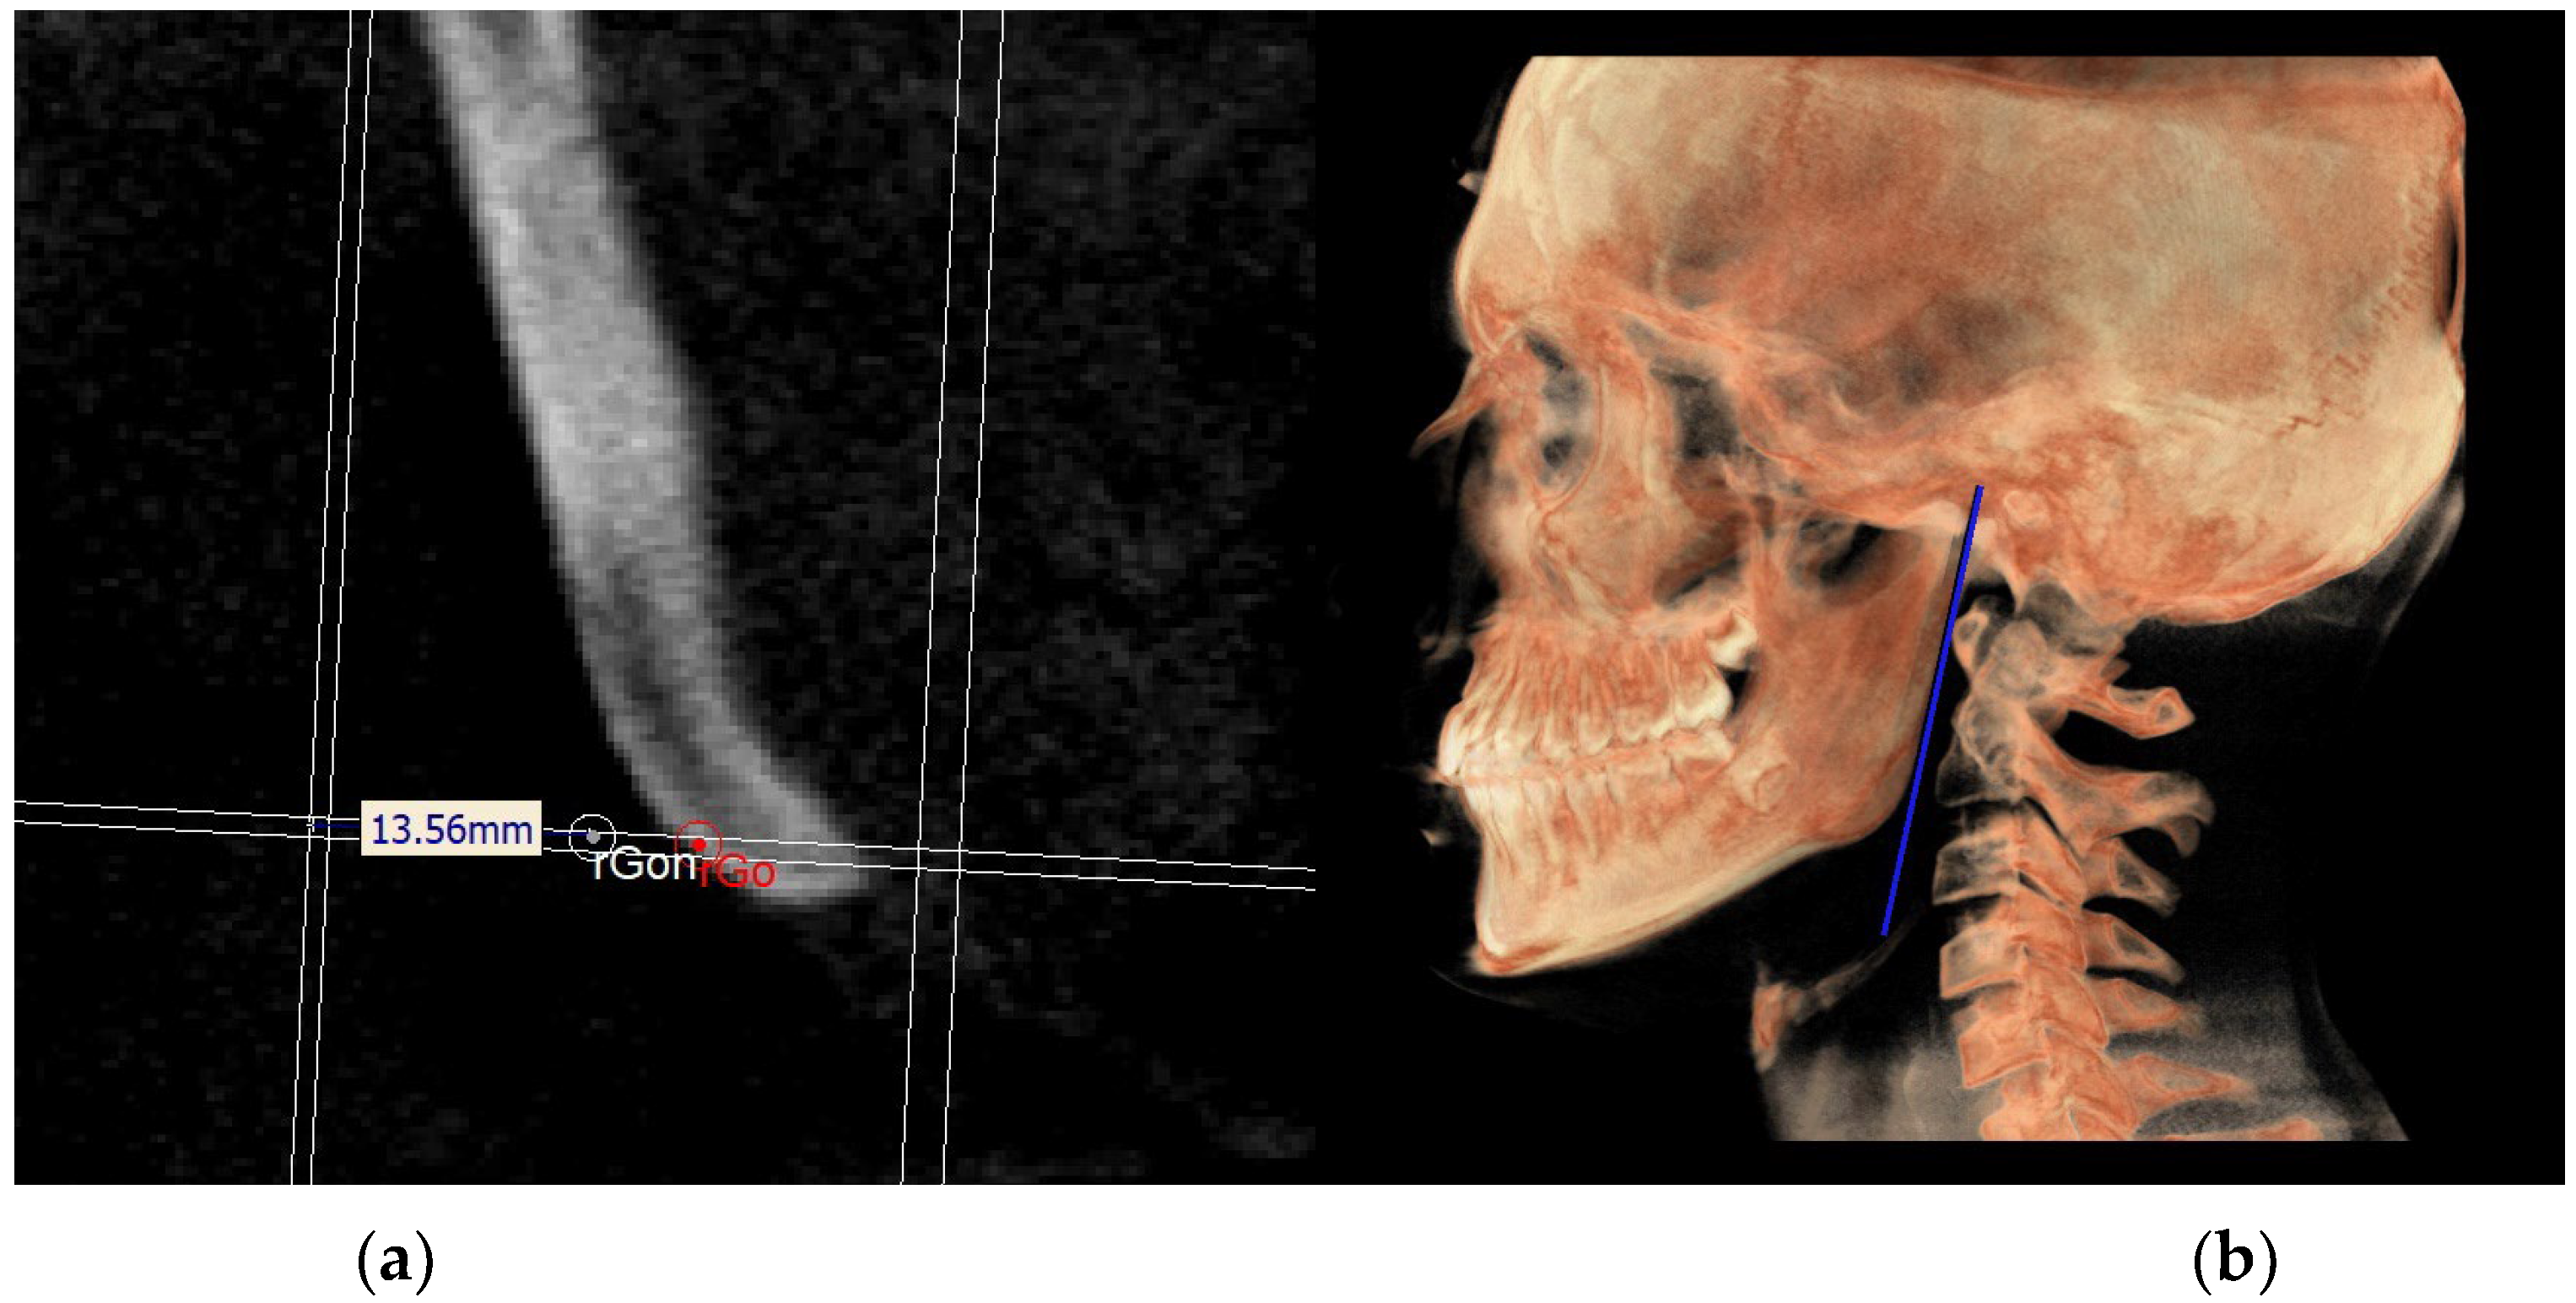

The mandibular ramus plane (MR) (Figure 5) was identified by the following points: the middle points between the right and left condylion (mCo) and the right Gonion (rGo) and left Gonion (lGo). To adequately locate the mCo, it is advisable to draw a line on the frontal view from the right condylion to the left one to have a reference along which measure the mid-distance;

Figure 5. Mandibular ramus plane.

Figure 15. Identification of rGon (a) and MRn on volume rendering (b).